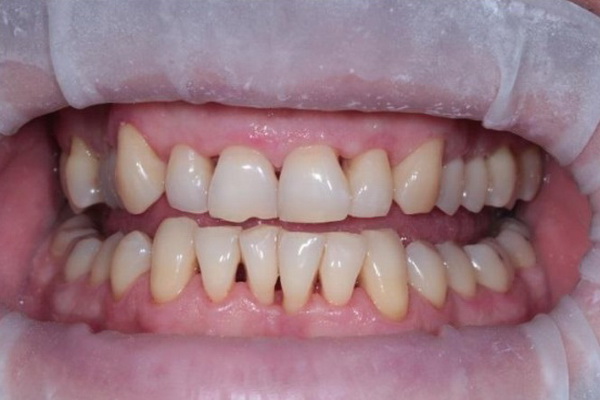

Такий був вигляд ясен пацієнта після лікування: ясна блідо-рожевого (природнього) кольору, не набряклі. Після видалення зубного каменю оголились поверхні коренів зубів: запалення в тканинах навколо зуба спричиняє руйнування кісткової тканини в якій знаходяться зуби, що призводить до опускання ясен на нижній щелепі та їх підйом на верхній щелепі.